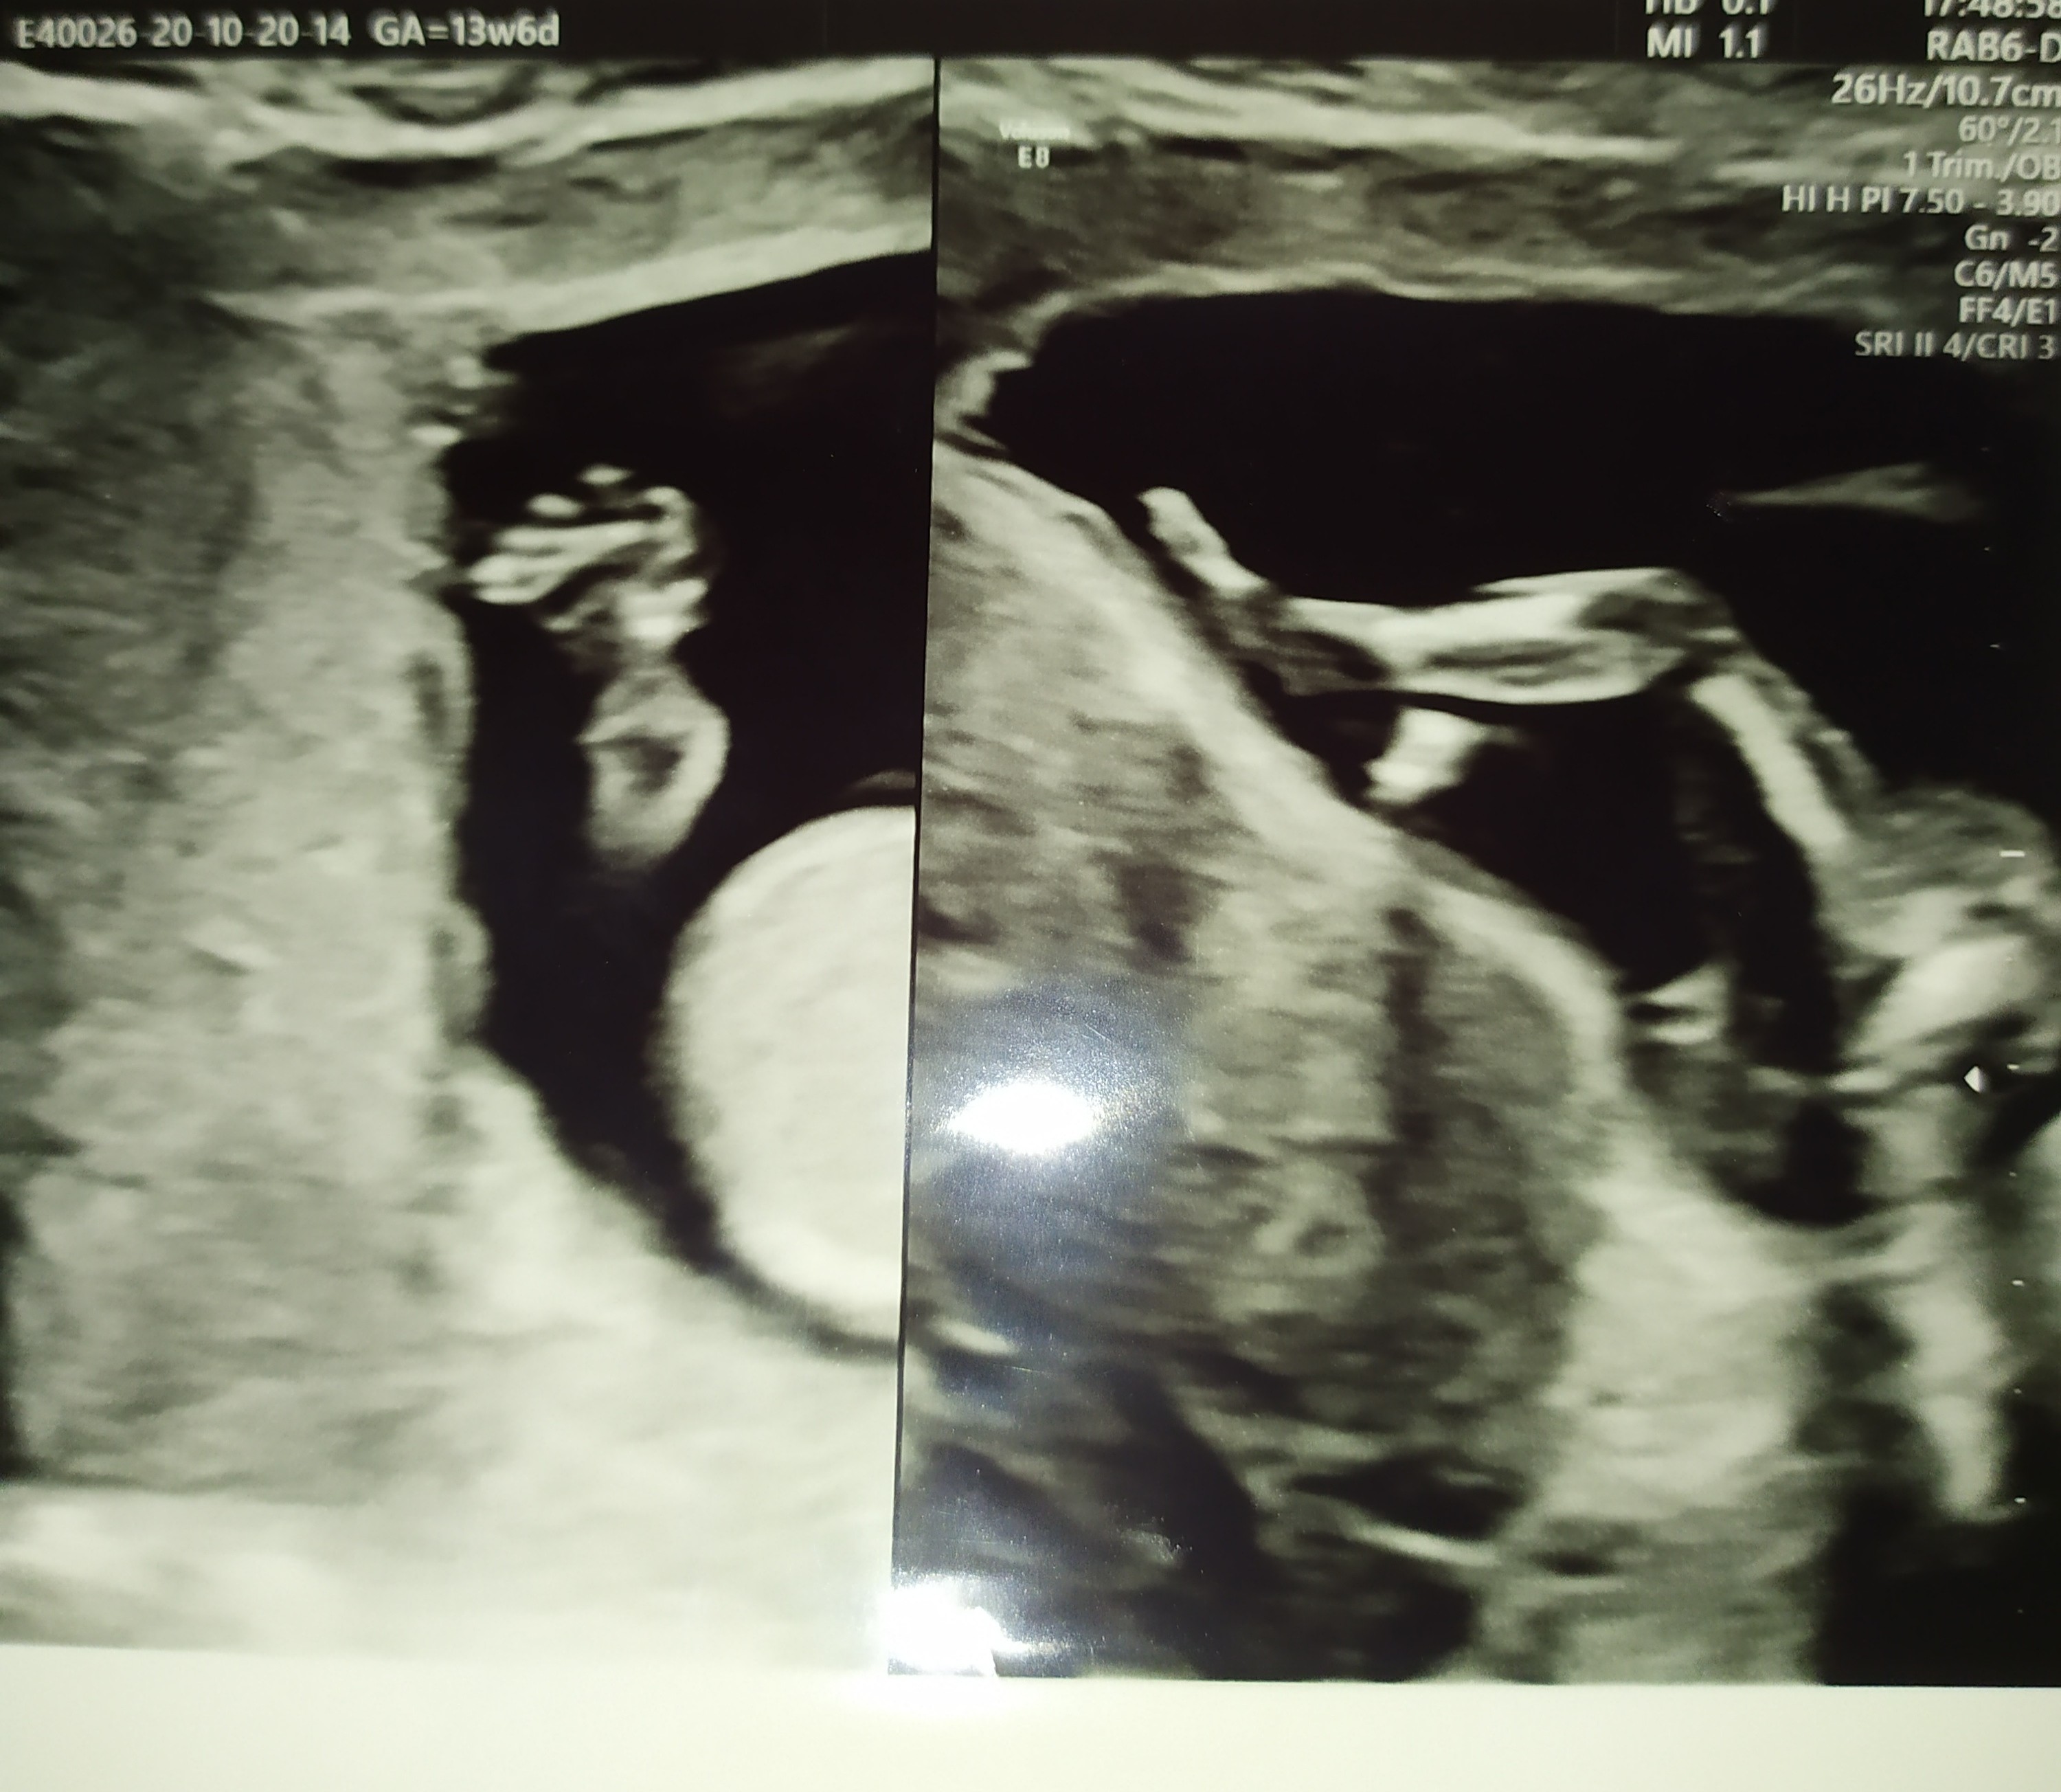

My po USG. Dzidzia książkowo rośnie, oczywiście wypinala dupsko, żebym tylko nie popatrzyła co ma w kroku 🙈😂

Wg wielkości dziecka niby 15tc, ale ogólne USG pokazuje na 14+5. Waży 105g🤔🤔🤔🤔 czy to jakoś nie za dużo? Czytałam ile na ten czas powinno mieć dziecko i piszą, że mniej. No, Ale lekarz powiedział, że rozwija się książkowo i Mu wierzę. A co mnie najbardziej ucieszyło , to to że miesniak zmalal 🥰 z 8cm do 7cm 😁

Witajcie, dzisiaj już trochę lepiej, leżę po śniadaniu żeby zostało ;) A zaraz do pracy. Odnośnie wczorajszego USG to lekarz był bardzo miły ( @Kamiśka :) nastawiałam się, że może być średnio ale chyba faktycznie miał wtedy gorszy dzień), wszystko pokazywał i objaśniał, nawet liczyliśmy palce u rączki [emoji2] Widziałam żołądek i pęcherz moczowy, serducho biło 152/min. Przezierność 1,8, ryzyko z wieku po USG spadło czterokrotnie :)Zobacz załącznik 1190837Zobacz załącznik 1190838Zobacz załącznik 1190839